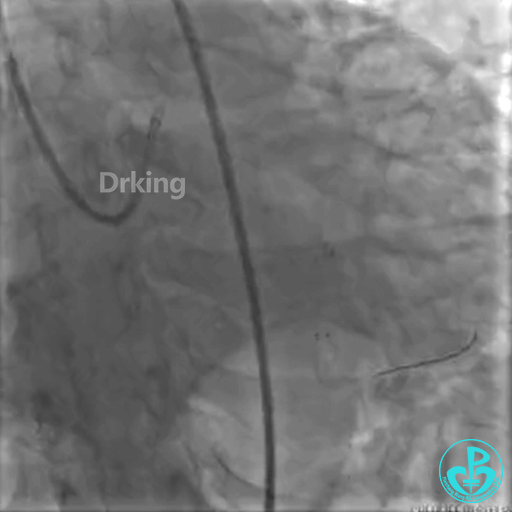

以下是导丝成功通过严重扭曲病变的图:

把Sion导丝送至高位OM的远段,在双腔微导管的辅助支撑下,把BMW导丝通过LCX扭曲及病变处顺利送至远段,撤出双腔微导管,2.0×20mm球囊对病变处PTCA后狭窄减轻,于病变处植入2.75×23mm支架一枚,后分别用2.75×12mm、3.0×12mm球囊对支架内后扩,复查造影原病变处狭窄消失,TIMI血流三级。